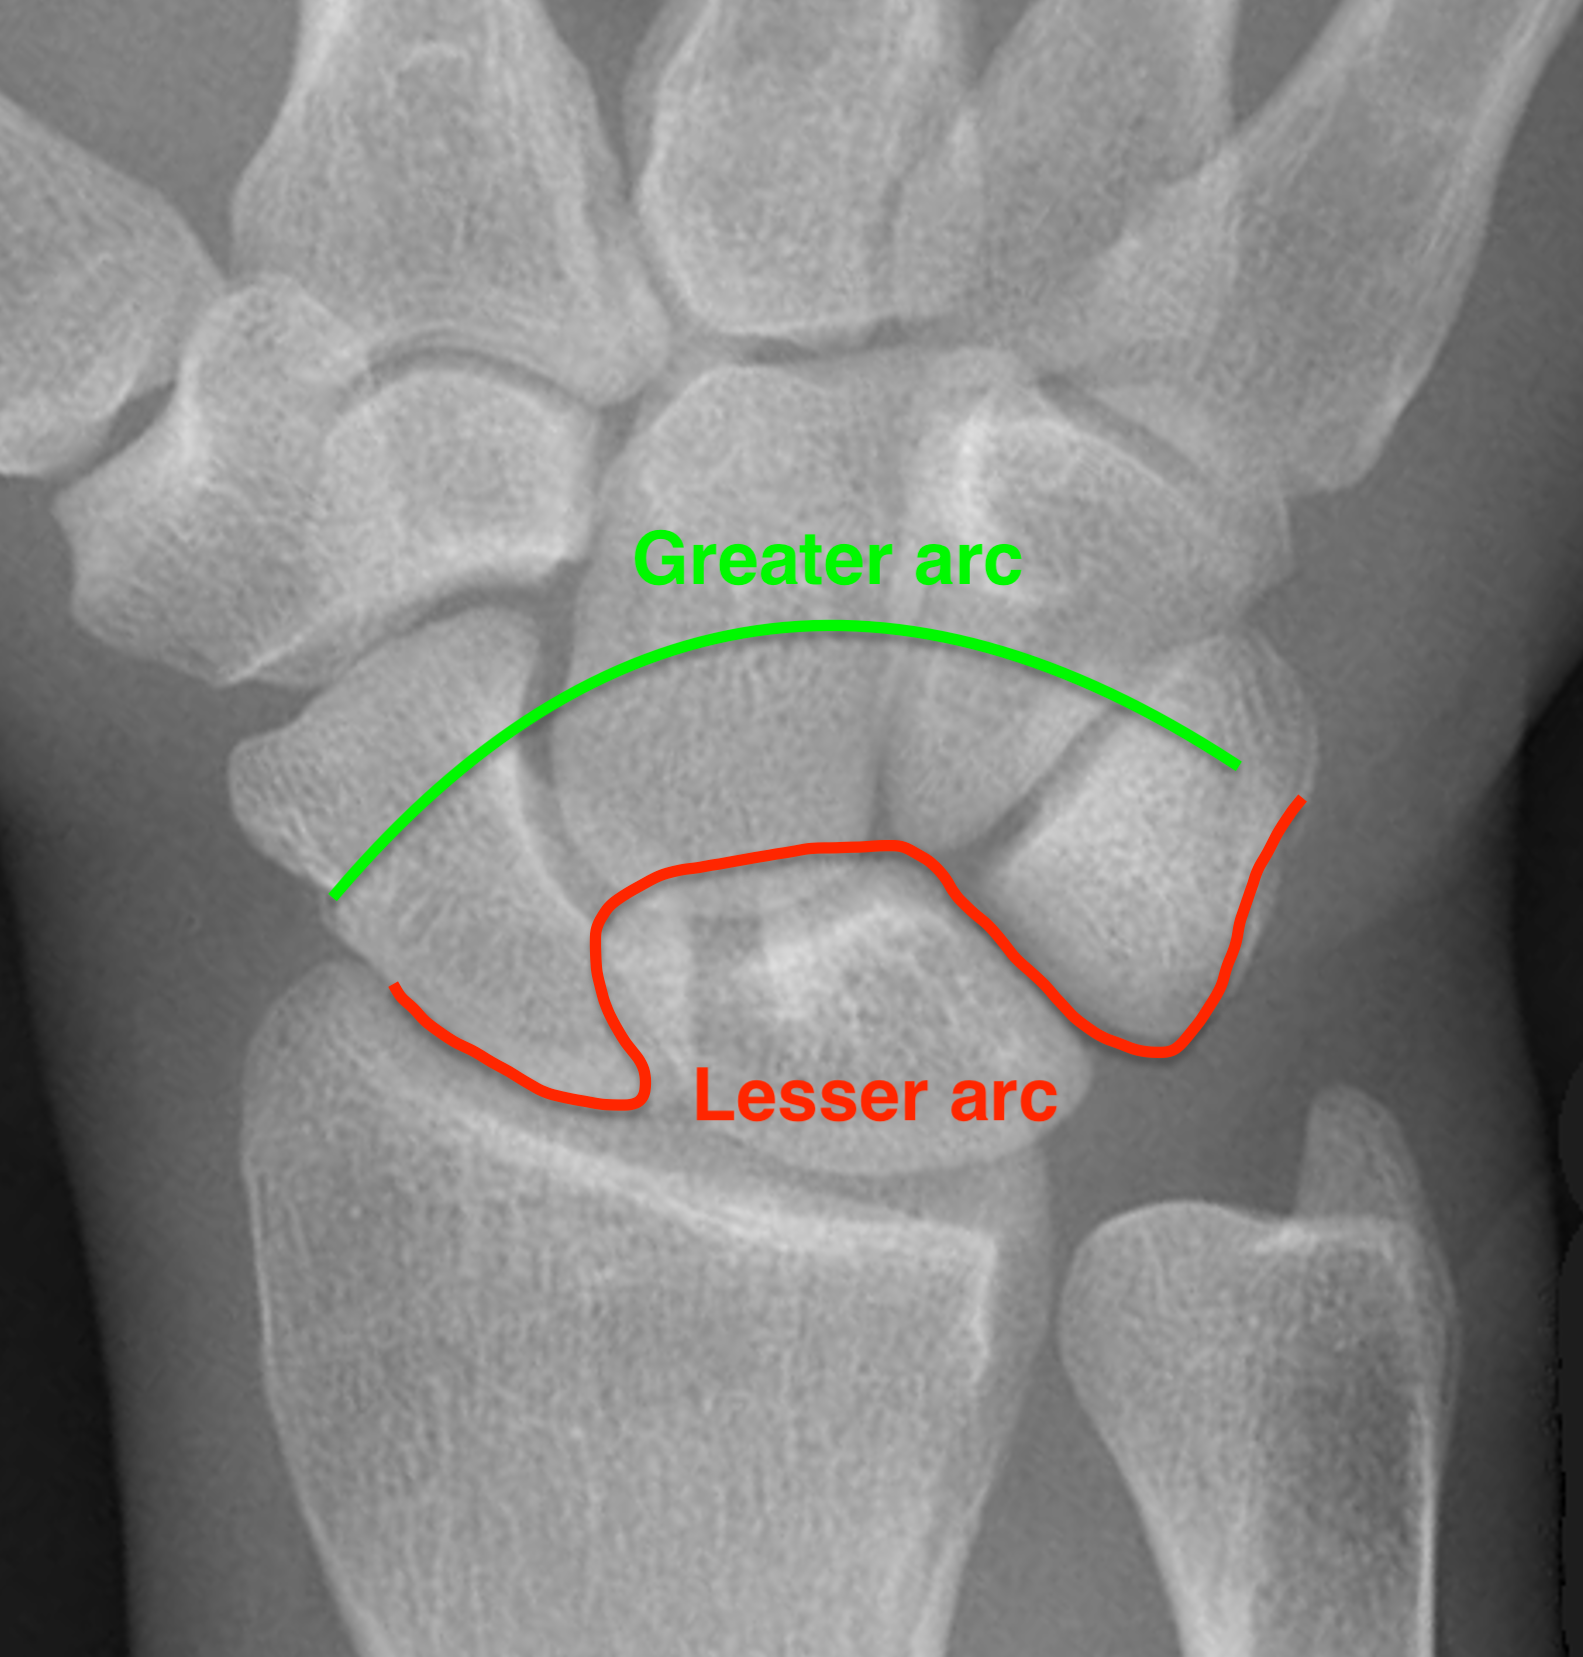

Gilula carpal arcs

Normally there are 3 smooth carpal arcs on PA xray

Arc I: Proximal cortical margins of proximal carpal row Arc II: Distal carpal margin of the proximal carpal row Arc III: Proximal cortices of the capitate and hamate |

Greater arc injuries - ligamentous injury + fracture - fractures of scaphoid / capitate / radial styloid - scaphoid most common, radial styloid second)

Lesser arc injuries - Purely ligamentous injuries around the lunate